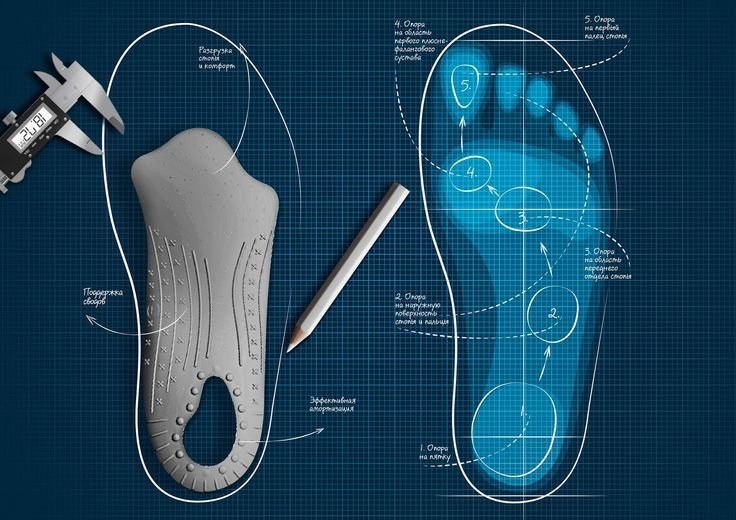

State-of-the-art equipment for precise foot analysis and custom orthotic solutions

3D Foot Scanning

We use high-precision 3D foot scanners to analyze:

- ✓ Foot pressure points

- ✓ Arch height

- ✓ Weight distribution

- ✓ Gait pattern

3D CAD Modelling

We design each insole digitally using German CAD modelling software to match your:

- Foot contour

- Pressure zones

- Medical requirements